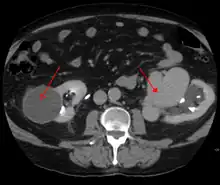

- Computerized tomography (CT) scan is a noninvasive X-ray to view the anatomical structures within the brain to detect blood in or around the brain. A newer technology called CT angiography involves the injection of contrast into the blood stream to view the arteries of the brain. This type of test provides the best pictures of blood vessels through angiography and soft tissues through CT.

AVMs can occur in various parts of the body:

- kidney[15]